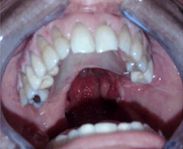

La prótesis es finalmente instalada (Fig. 13)realizándose los controles correspondientes tanto protésicos como fonoaudiológicos.14